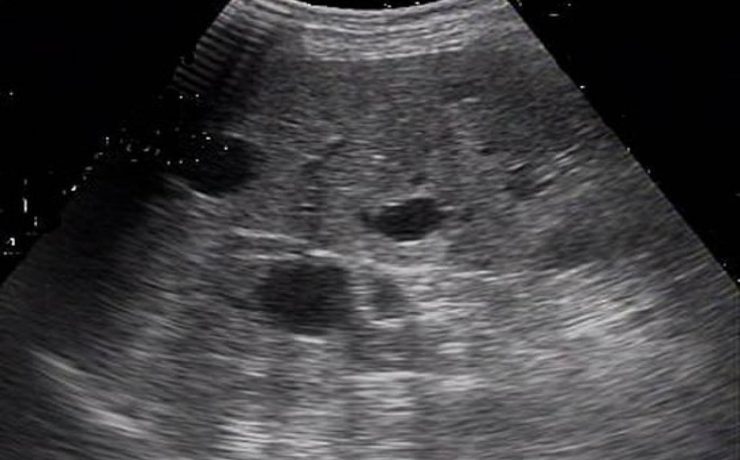

La equinococosis alveolar es causado por el metacestodo Equinococcus multilocularis, en los humanos proliferan en el hígado, induciendo un crecimiento lento progresivo semejante a un tumor. La infección ocurre en todos los continentes, cursa como una infección crónica con estado latente e incluso más de un tercio con detectados incidentalmente,